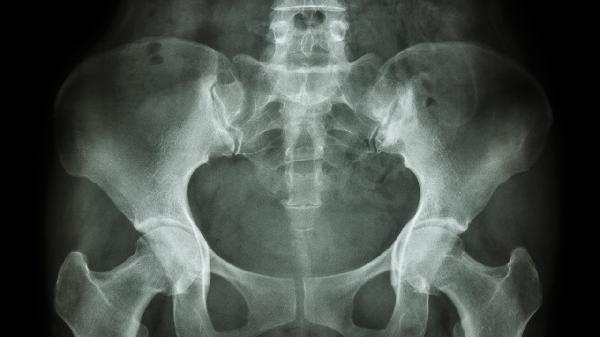

83岁老人骨盆骨折怎么治

83岁老人骨盆骨折可通过保守治疗、药物治疗、手术治疗等方式处理。骨盆骨折通常由外伤、骨质疏松等因素引起,可能伴随疼痛、活动受限等症状。

老年骨盆骨折患者需定期复查X线观察愈合情况,卧床期间每2小时翻身一次预防压疮,保持会阴清洁避免尿路感染。家属应协助进行日常护理,注意观察下肢肿胀、疼痛变化,出现异常及时就医。恢复期避免跌倒等二次伤害,建议使用防滑垫、扶手等适老化改造设施。